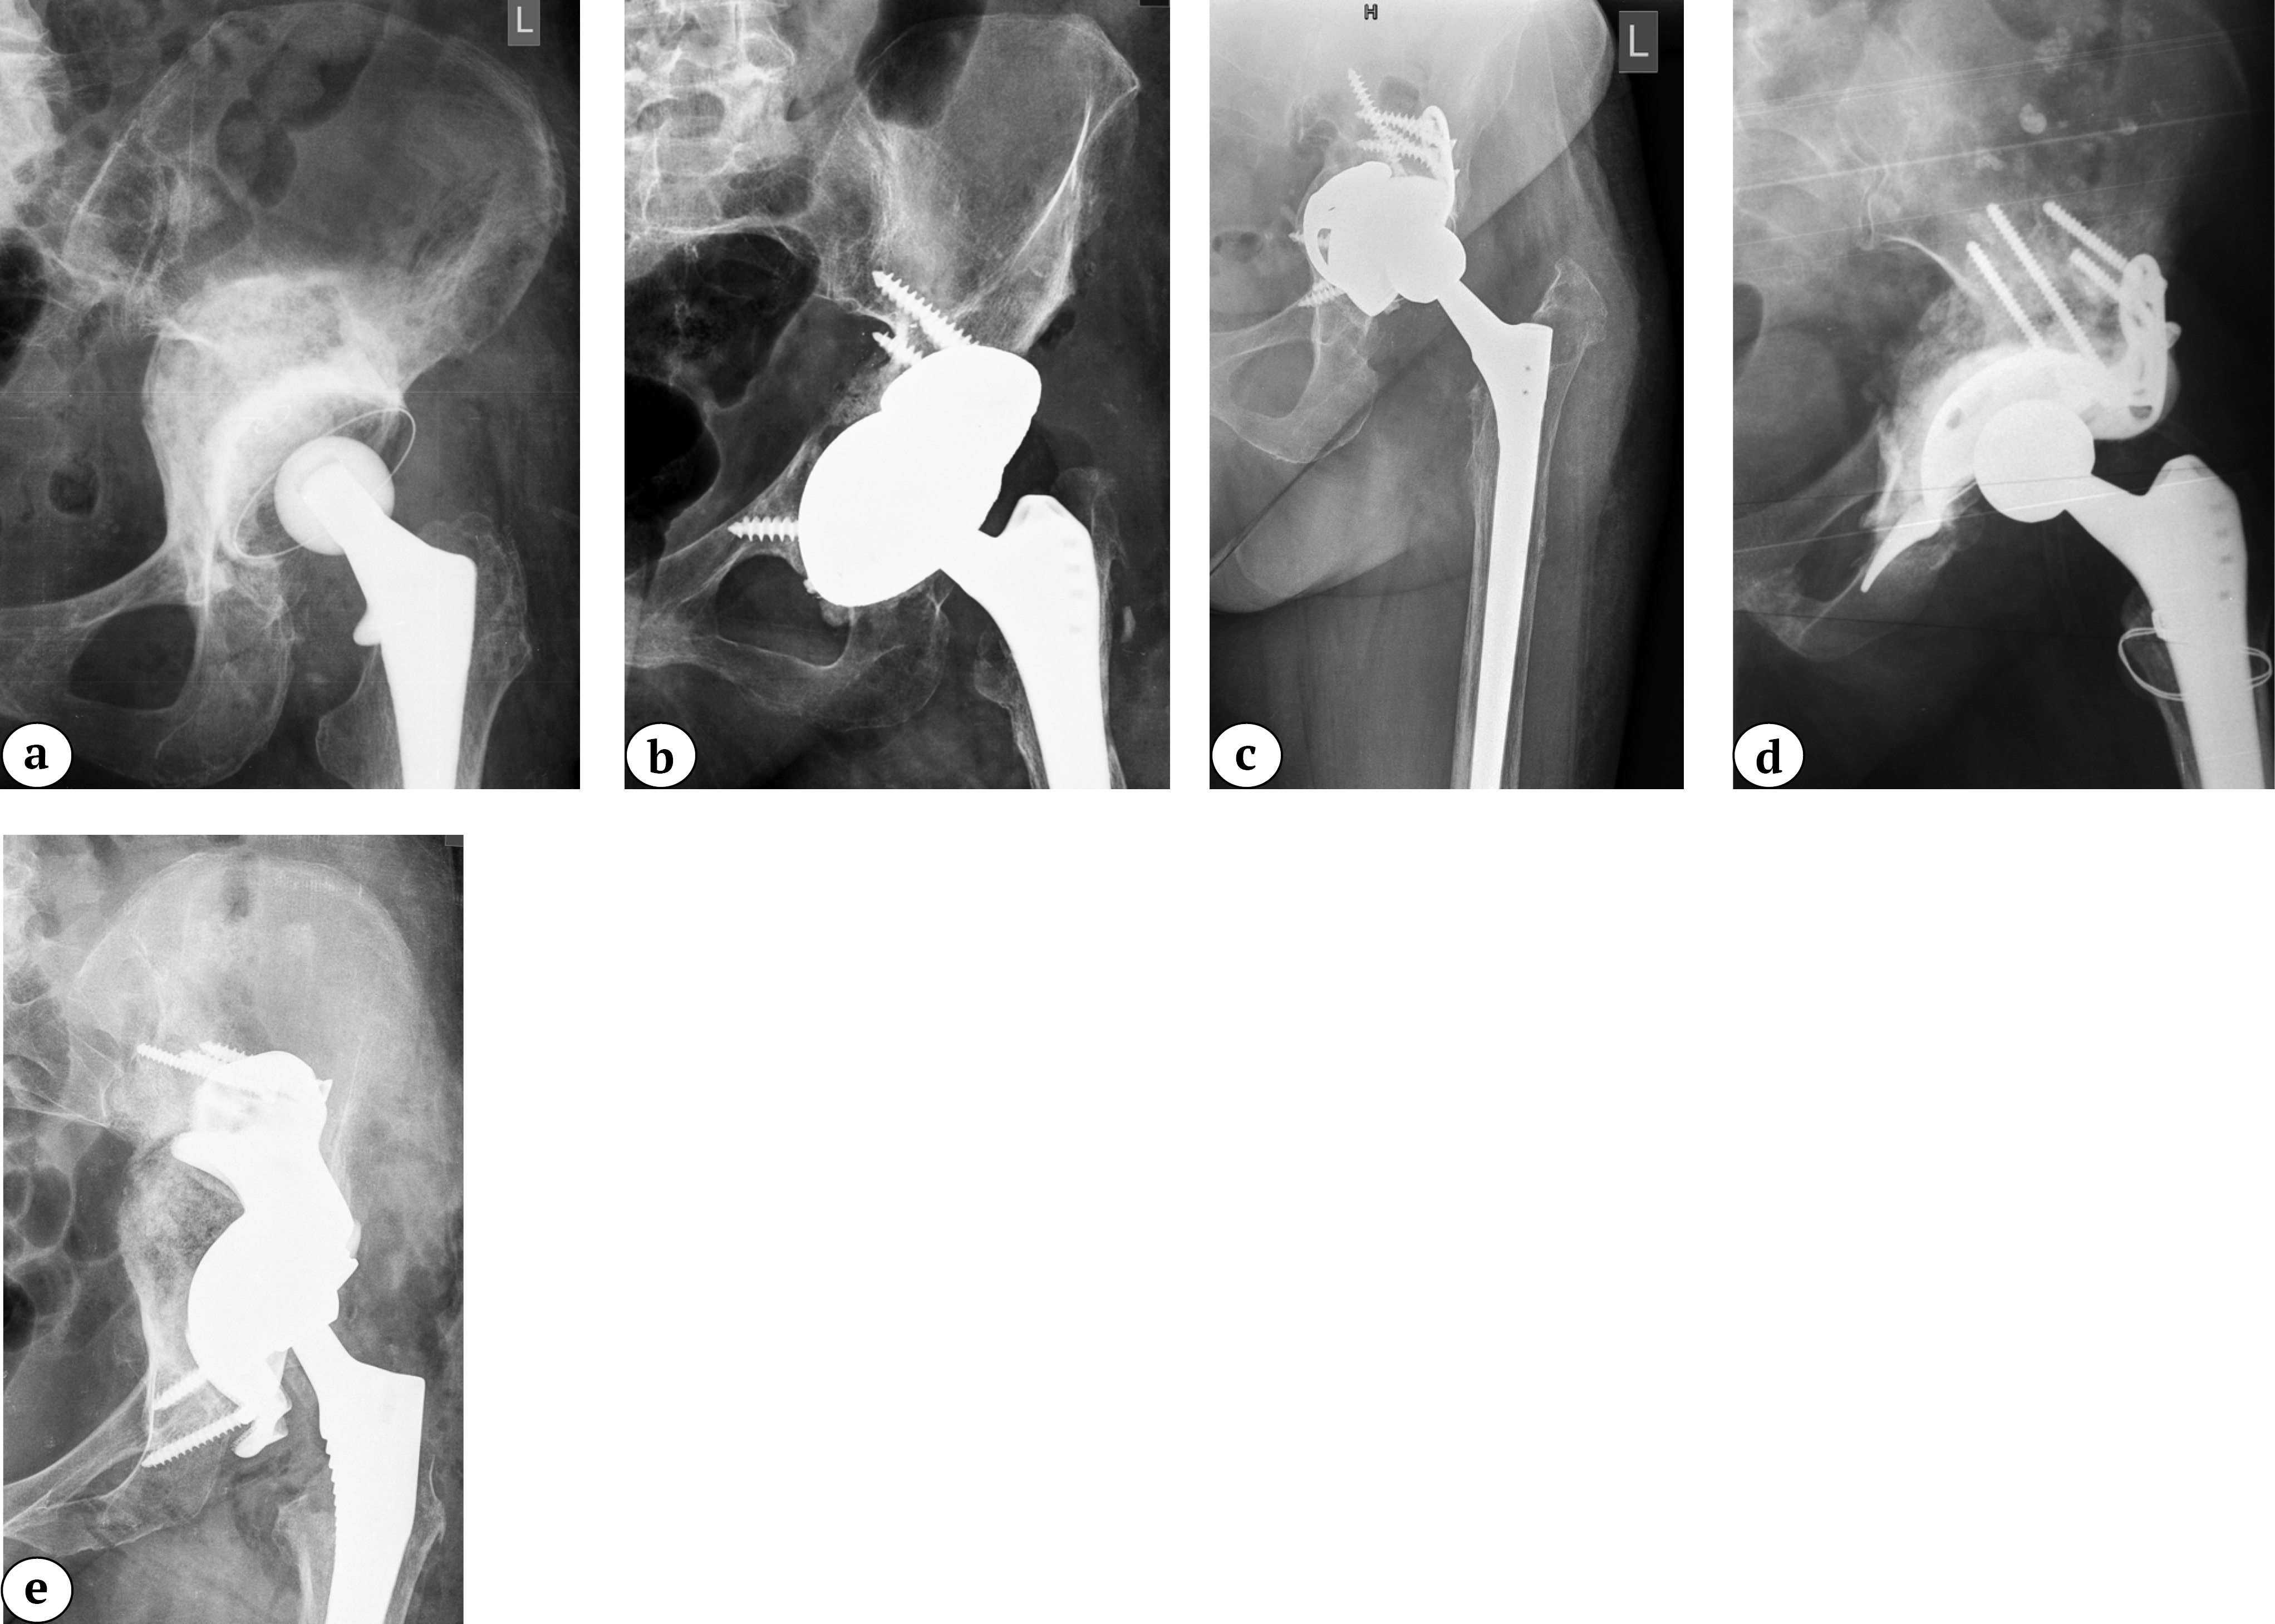

X-rays of patients with defects | ||||

Three-dimensional reconstructions of the pelvis of the same patients from the side of defect | ||||

Lytic defects and complete defects of the anterior column, despite their extent, require the restoration of the sphericity of the acetabular region, which can be reconstructed using bone grafts, augments, and standard hemispherical components (Figure 2 a, b).

Figure 2. Various options for acetabular reconstruction in Paprosky type 3B defect: a — lytic acetabular defect reconstructed using impaction bone grafting with implantation of a standard cemented acetabular component; b — complete anterior column defect reconstructed with an augment and a hemispherical acetabular component; c — complete medial wall defect reconstructed with augmentation and combined implantation of a hemicap cage; d — combination of complete medial wall and anterior column defects reconstructed with a Burch-Schneider antiprotrusio cage and a cemented acetabular component; e — combination of complete medial wall and posterior column defects reconstructed with a patient-specific acetabular component

Reconstruction of complete medial wall defects, as well as combined complete defects of the medial wall and anterior column, requires the use of antiprotrusio devices to ensure the stability of the acetabular component. For this combination of defects, a wide range of types and sizes of standard cages may be necessary (Figure 2 c, d). In cases of combined complete defects of the medial wall and posterior column — the most challenging in terms of biomechanical stability of the acetabular component — there is a need for a highly reliable primary fixation of the implant, which cannot always be achieved with standard revision systems (Figure 2 e).